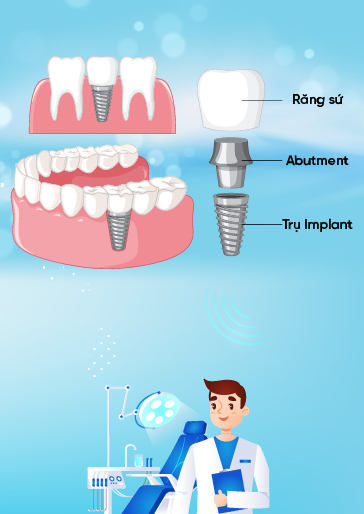

- Chứng nhận “Dịch Vụ Hoàn Hảo” dành cho dịch vụ Cấy Ghép Implant và Phục Hình Răng Sứ do chính khách hàng bình chọn.